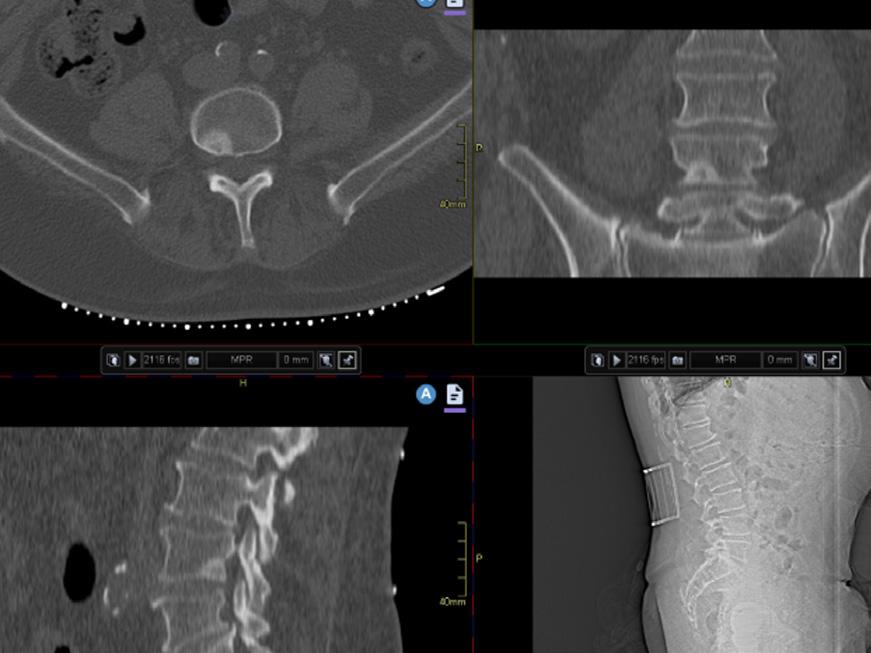

reduceras en hel del utan påverkan på bildkvaliteten eftersom skelett har en hög inneboende kontrast visavi omgivande mjukdelar. Det är fullt möjligt att göra CT till samma organdos som för röntgenundersökning, till exempel ländrygg2 vilket ger en CT av förhållandevis låg kvalitet med hög brusnivå, men som ändå ger mera diagnostisk information än motsvarande röntgenundersökning tack vare den tomografiska metoden och tredimensionell datavolym. Det kan dock krävas en del justeringar av inställningar för att få en så bra lågdosundersökning som möjligt. Bild 3.

Bild 3. Lågdos-CT av en äldre patient med långdragen ankyloserande spondylit med ankylos i kotpelare och sacroiliacaleder. Sagittal reformatering och 3D-rekonstruktion. Bild 4. Cone-beam-CT med stol för patienten och vinklat gantry. Foto Mats Geijer.

till exempel uratutfällningar vid gikt kartläggas (Bild 6) och benmärgsödem vid trauma avbildas och ger en bild liknande den vid MRT3 (Bild 7). Det finns många andra frågeställningar där DECT kan användas.

Men även konventionell CT kan påvisa benmärgsödem, främst hos osteoporotiska äldre med höftfraktur eller kotfraktur där ett benmärgsödem kontrasterar tydligt mot bakgrunden av fetthaltig gul benmärg.4,5 Vid misstänkt ockult höftfraktur hittar man fler frakturer med hjälp av benmärgsödem än med hjälp av kortikala frakturer. Det krävs att man använder ett mjukdelsfönster (bukfönster) vid granskningen. Diagnostiken underlättas också om undersökningen är gjord med en medelmjuk rekonstruktionsalgoritm utan för mycket kantförstärkning och om man vid misstänkt höftfraktur har tillgång till jämförande bilder från den andra höften. Bild 8.

man med inkomplett höftfraktur. A) T1-viktad MRT visar frakturlinje från trochanter major i distal riktning (pilhuvuden), B) MRT med STIR-sekvens visar benmärgsödem i samma område, C) konventionell CT visar benmärgsödem (pilar) som ett ljust högattenuerande område som framträder tydligt mot den annars mörka och lågattenuerande fetthaltiga gula benmärgen.

Segondfraktur. DECT visar benmärgsödem i laterala tibiakondylen och mediala femurkondylen samt i anslutning till eminentia intercondyloidea som ljusa områden.